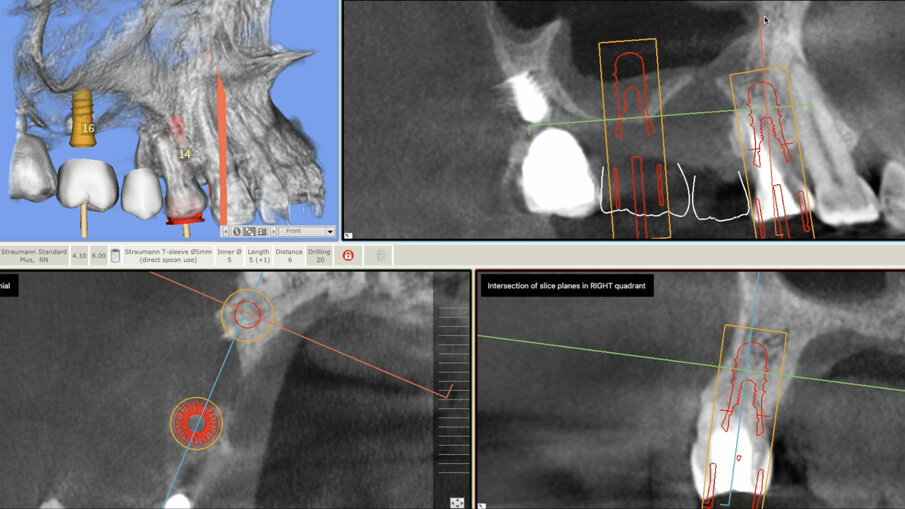

All’esame clinico e radiografico (Figg. 1, 2), si riscontra la persistenza della lesione endo-parodontale in sede 1.4, la presenza di un’atrofia ossea verticale nella cresta ossea edentula 1.5 associata a una deiscenza del pavimento sinusale sul fondo del difetto, e la presenza di una perimplantite severa a livello dell’impianto 1.7. Si riscontra inoltre una pneumatizzazione del seno mascellare destro in sede 1.6, con un’altezza ossea residua di ca. 1,5 mm.

Eseguita la ceratura digitale del caso e riscontrata la presenza di una quota ossea residua incompatibile con l’inserimento di impianti in posizione protesicamente guidata, si progetta un intervento combinato di:

A distanza di 6 mesi, previa acquisizione di una CBCT (Figg. 8-10), si procede con il rientro chirurgico nella sede ricostruita (Fig. 11). Scheletrizzato il mascellare ricostruito, si riscontra una parziale risoluzione del difetto verticale in sede 1.5 e il ripristino di volumi ossei idonei all’inserimento di impianti in posizione protesicamente guidata in sede 1.4 ed 1.6. Durante la preparazione dei letti implantari, si esegue il prelievo di due carote ossee mediante fresa trephine da 3.3 mm. Segue quindi l’inserimento di due impianti Tissue Level SP 4.1 x 8 mm (Straumann) e l’adozione di un protocollo di guarigione sommerso (Figg. 12, 13).

Fig. 9 - CBCT al baseline e a 6 mesi - ricostruzione 3D.

; Fig. 10 - CBCT al baseline e a 6 mesi - visione assiale e para-sagittale.